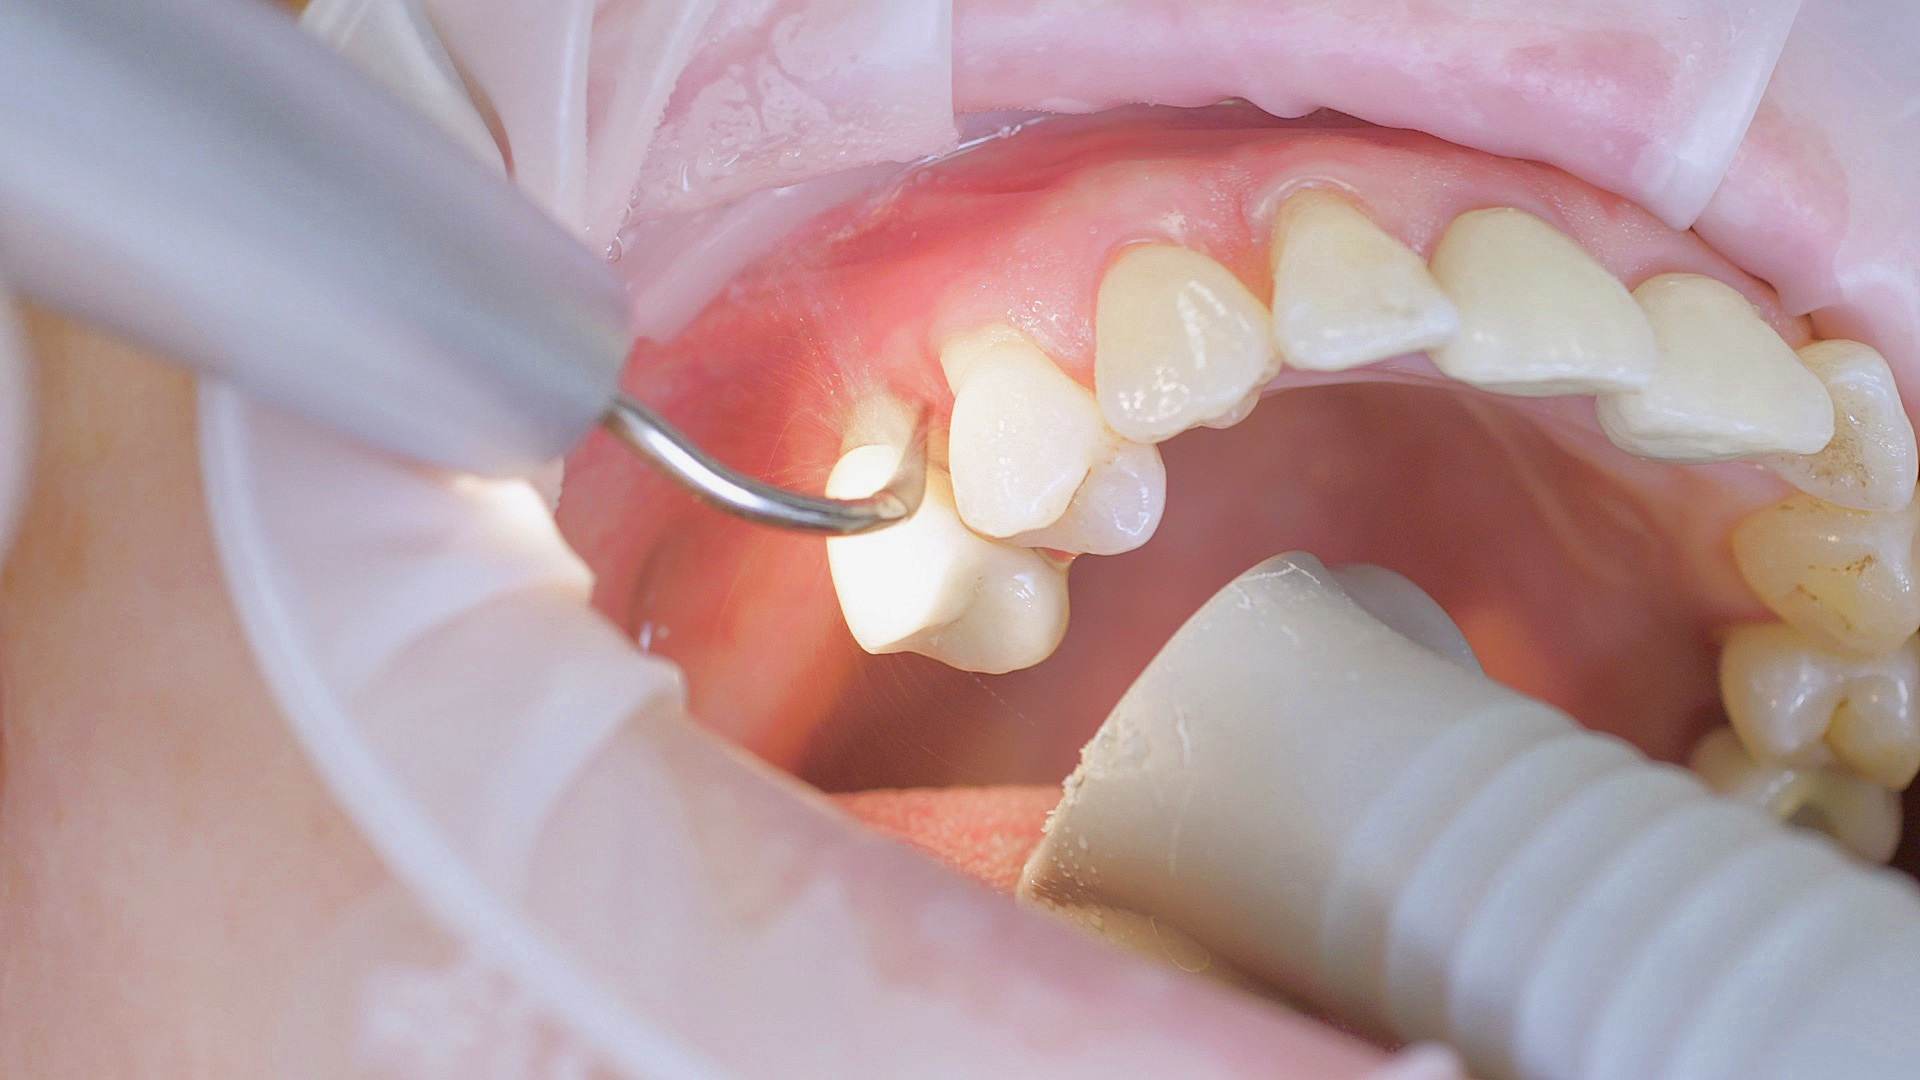

Lors des soins postopératoires ou d’un traitement non chirurgical, les implants et les superstructures peuvent être nettoyés à l’aide d’appareils à ultrasons et d’instruments en plastique spécifiques.

Fig. 3 : Lors des soins postopératoires ou d’un traitement non chirurgical, les implants et les superstructures peuvent être nettoyés à l’aide d’appareils à ultrasons et d’instruments en plastique spécifiques.

Lorsqu’il est sain, le tissu péri-implantaire ne montre aucun signe de rougeur, de gonflement ou de saignement et l’examen ne révèle aucune formation de pus.[5] À partir du document de consensus, le Pr Giovanni Salvi a justifié l’importance d’un examen régulier — de préférence à l'aide d’une sonde flexible, car les éléments de l'implant ont tendance à gêner l'accès au site d’intervention.[5] Dans le cas d’une mucite ou d’une péri-implantite initiale déjà présentes, il convient dans un premier temps de tenter d’éliminer par une méthode non chirurgicale les dépôts durs et le biofilm. Pour ce faire, on utilise des instruments à ultrasons et spéciaux conçus pour protéger l'implant (Fig. 3 ; détartreur piézo Tigon+ avec 1I, W&H). En l'absence de rémission, la fréquence de suivi doit être augmentée. Toutefois, aucune recommandation spécifique, applicable au cas par cas, n’a encore été donnée dans ce contexte.[15]